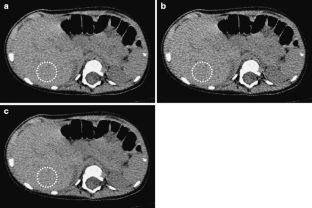

Fig 3.